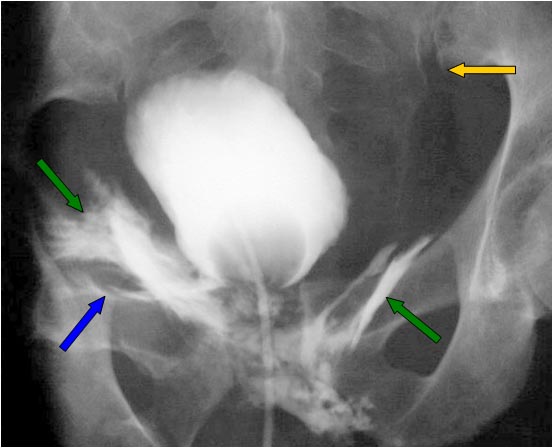

SIGNO DEL RESPLANDOR SOLAR

Signo de rotura vesical extraperitoneal en la cistografía. La extravasación del contraste hacia los tejidos blandos extraperitoneales y, especialmente hacia el espacio prevesical de Retzius, da un aspecto característico de «llamaradas» o «resplandor solar“ (flechas verdes).

Obsérvese la fractura de rama ilio-pubiana derecha (flecha azul) y la diástasis de la articulación sacroilíaca izquierda (flecha amarilla).